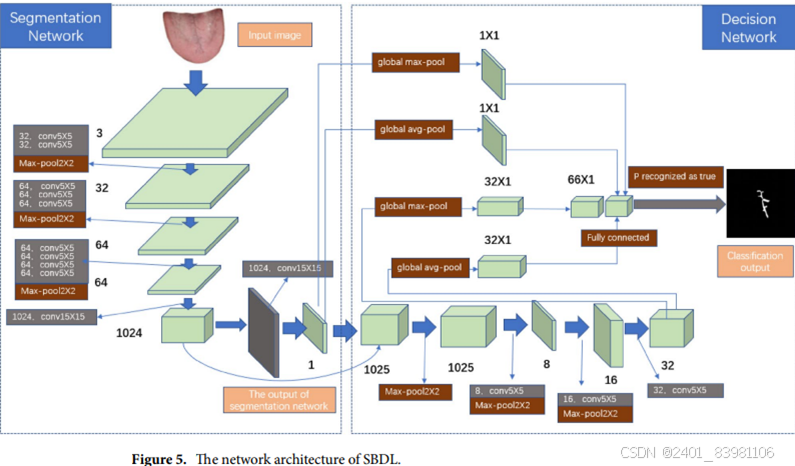

单独应用深度学习网络SBDL来提取和识别舌头裂缝 ,如图:

- 采用目标检测和舌象高分辨率特征的双阶段舌象分割方法,mIoU可达98.2%;

如改进的 YOLO V4-tiny 舌像定位检测算法,更适于小目标检测(K-Means ,模糊C均值)但精度,速度低(已改进GCYTD 算法) 采用粗分割网络 Rsnet定位舌体,精分割网络Fs-net对定位的舌体进行精细分割,最高F值超过99%。